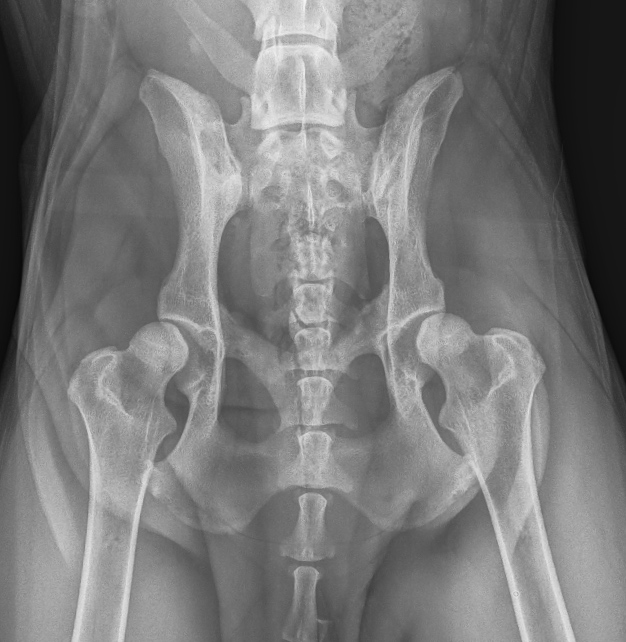

The Whyalla Veterinary Clinic has a new Shimadzu MUX10 Xray machine for high quality radiographs and a new Agfa XD14 Csi Tethered panel to produce outstanding direct digital Xrays from the images from the Shimadzu MUX10 Xray machine.

The XD14 CsI Tethered Panel is an integral part of an Agfa HealthCare’s Instant DR solution, which includes the NX image acquisition software with MUSICA3 processing and detector. These cassette-less and filmless solutions provide a range of workflow benefits that improve quality, productivity and speed up exam time.